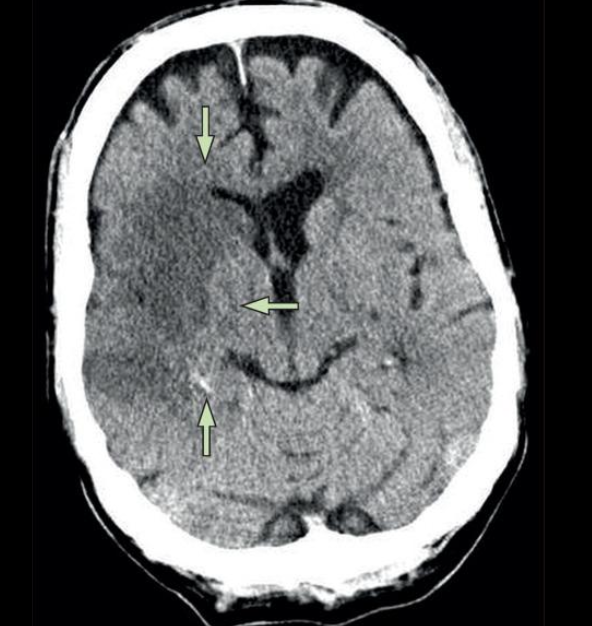

22

Q

A

EVC hemorragico

HSA